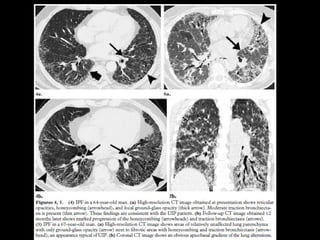

AIP • Rápidamente progresiva •Persona sana en días o semanas • DAD de causa desconocida • DD: SDRA • Ventilación mecánica O2 • 50% mortalidad

AIP CT • Vidrioesmerilado • Simétrico, bilateral LI • Consolidaciones • Tardía hay distorsión, bq x tracción y panalización • DD: SDRA, COP, P jirovecii, edema hidrostático, neumonía eosinofílica aguda, hemorragia alveolar difusa, proteinosis alveolar.